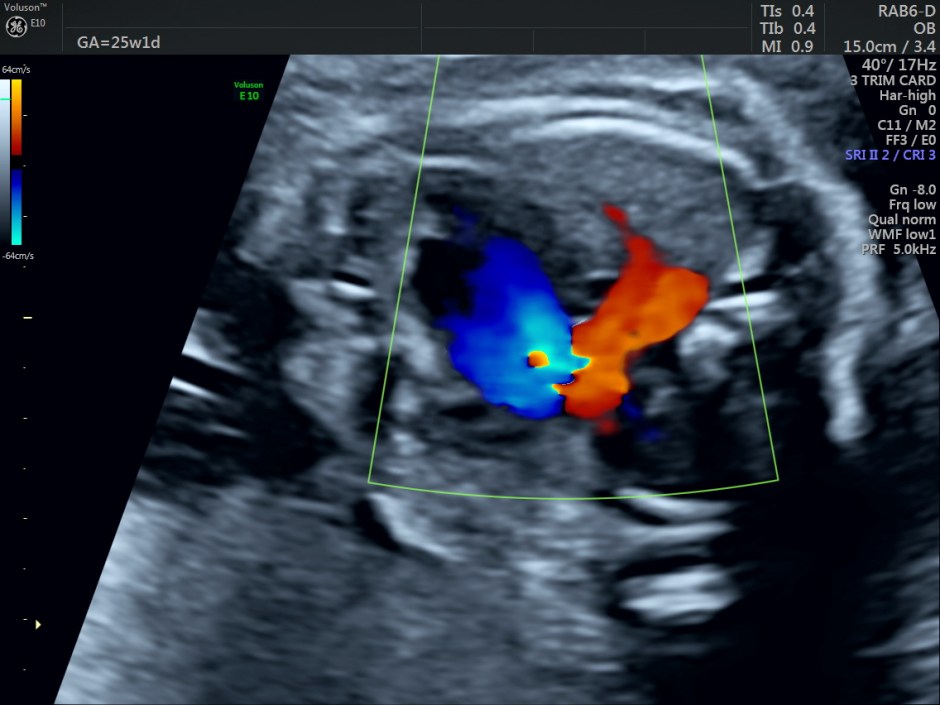

The right ventricular inflow is seen in the following picture.

The left ventricle appears very small.

The right ventricular outflow is seen in this picture.